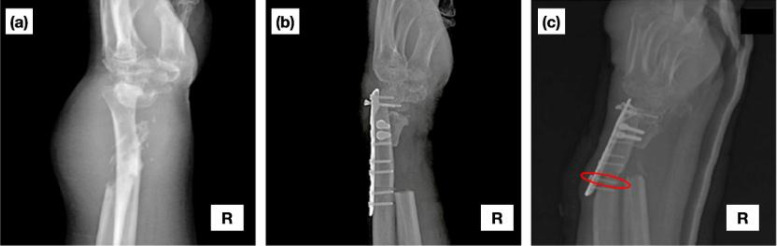

桡骨远端骨折通常需要手术干预,钢板固定是一种标准的稳定方法。螺钉松动和拔出会引起严重的并发症,需要全面了解固定稳定性因素。本研究采用有限元分析(FEA)和Thiel尸体实验研究相结合的新方法来评估桡骨远端整体切除尺骨重建钢板固定后螺钉拔出行为。与以往使用计算模型或新鲜冷冻尸体标本的研究相比,在本研究中,FEA预测专门通过实验证实了Thiel尸体的使用,它更好地保留了软组织的弹性和水合性,从而更接近地反映了体内情况。实验设置包括尸体弯曲试验和thiel -尸体桡骨标本上的螺钉拔出试验,模拟诱发螺钉拔出效应的生理条件。结合实际临床病例进行有限元分析和仿真。生物力学测试结果显示锁定板变形和螺钉松动,特别是在最接近尺骨间隙的位置。扭矩测量确定了不同程度的螺钉松动,最靠近骨间隙的螺钉表示最大程度的松动。有限元分析证明了螺钉和锁紧板的临界应力分布,与实验结果有很好的相关性。螺钉拔出力分析显示易松动,特别是在骨间隙区域,生物力学测试和有限元分析结果一致。本研究为整块桡骨远端切除尺骨重建钢板固定的手术意义和生物力学考虑提供了有价值的信息。

Fractures of the distal radius often require surgical intervention, with plate fixation being a standard stabilization method. Screw loosening and pull-out propose significant complications, necessitating comprehensive understanding of fixation stability factors. This study introduces a novel approach by the combination of finite element analysis (FEA) and experimental investigations on Thiel cadavers to evaluate screw pull-out behavior from plate fixation in en bloc distal radius resection with ulnar reconstruction. In comparison with previous investigations that used computational modeling or fresh-frozen cadaveric specimens, in the present research, FEA predictions specifically experimentally confirm the usage of Thiel cadavers, which better preserve soft tissue elasticity and hydration, thus more closely reflect in vivo conditions. Experimental set-up consisted of bending tests on cadavers and screw pull-out tests in Thiel-cadaveric radius specimens mimicking physiological conditions that induce the effects of screw pull-out. Finite element analysis and simulation were conducted using realistic clinical cases. Biomechanical test results indicated locking-plate deformation and screw loosening, particularly at locations closest to the ulnar bone gap. Torque measurements established various degrees of screw loosening, with the screws closest to the bone gap indicating maximum loosening. FEA demonstrated critical distributions of stresses in screws and locking plates, with good correlations to experimental findings. Screw pull-out force analysis showed vulnerability to loosening, particularly in the area of bone gaps, with findings consistent between biomechanical testing and FEA. This study offers valuable information on the surgical implications and biomechanical considerations of plate fixation for en bloc distal radius resection with ulnar reconstruction.